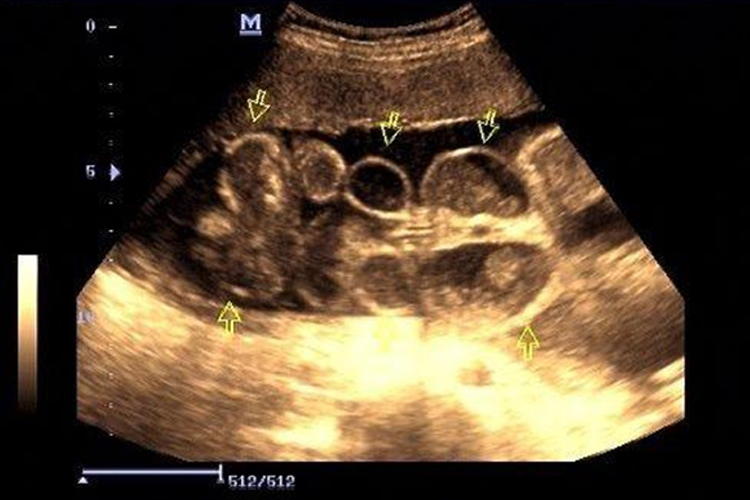

1、胎儿解剖结构检查:大排畸检查会仔细查看胎儿的头部、面部、脊柱、心脏、肺、肝、胃、肾、膀胱、肠、四肢等各个器官和部位,以确认是否存在结构上的异常或畸形,例如通过成像技术可以观察胎儿是否存在脑积水、脊柱裂、心脏结构异常等问题。

4、特殊检查项目:除了常规检查项目外,大排畸检查还可能包括一些特殊检查,如胎儿心脏超声检查,以更准确地评估胎儿心脏的功能和结构。